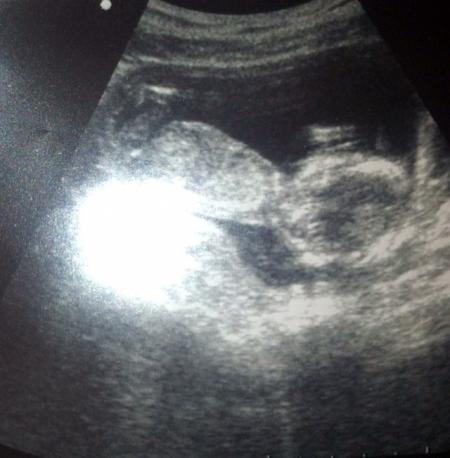

Ich bin voll neidisch auf das gute Schall Gerät :( Bei uns hat man nicht mal das Gesicht so wirklich sehen können nur Umrisse .. Find ich doof dabei bin ich ab Samstag schon in der 19. Woche ... Da musste man doch eig schon was erkennen ... :/

Bild zu